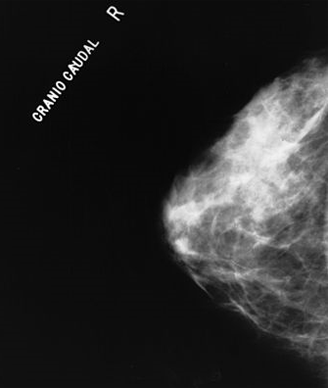

A Swedish study found that 3D tomosynthesis screening detected 40% more cases of breast cancer compared with traditional digital mammography.

Tomosynthesis uses three-dimensional x-rays and, like tomography, can show multiple thin layers of the breast from different angles. The method is more costly than traditional mammography, but it can reduce patient discomfort and pain, as the breast does not need to be as compressed during the imaging process. Tomosynthesis also delivers lower doses of radiation than traditional mammography.